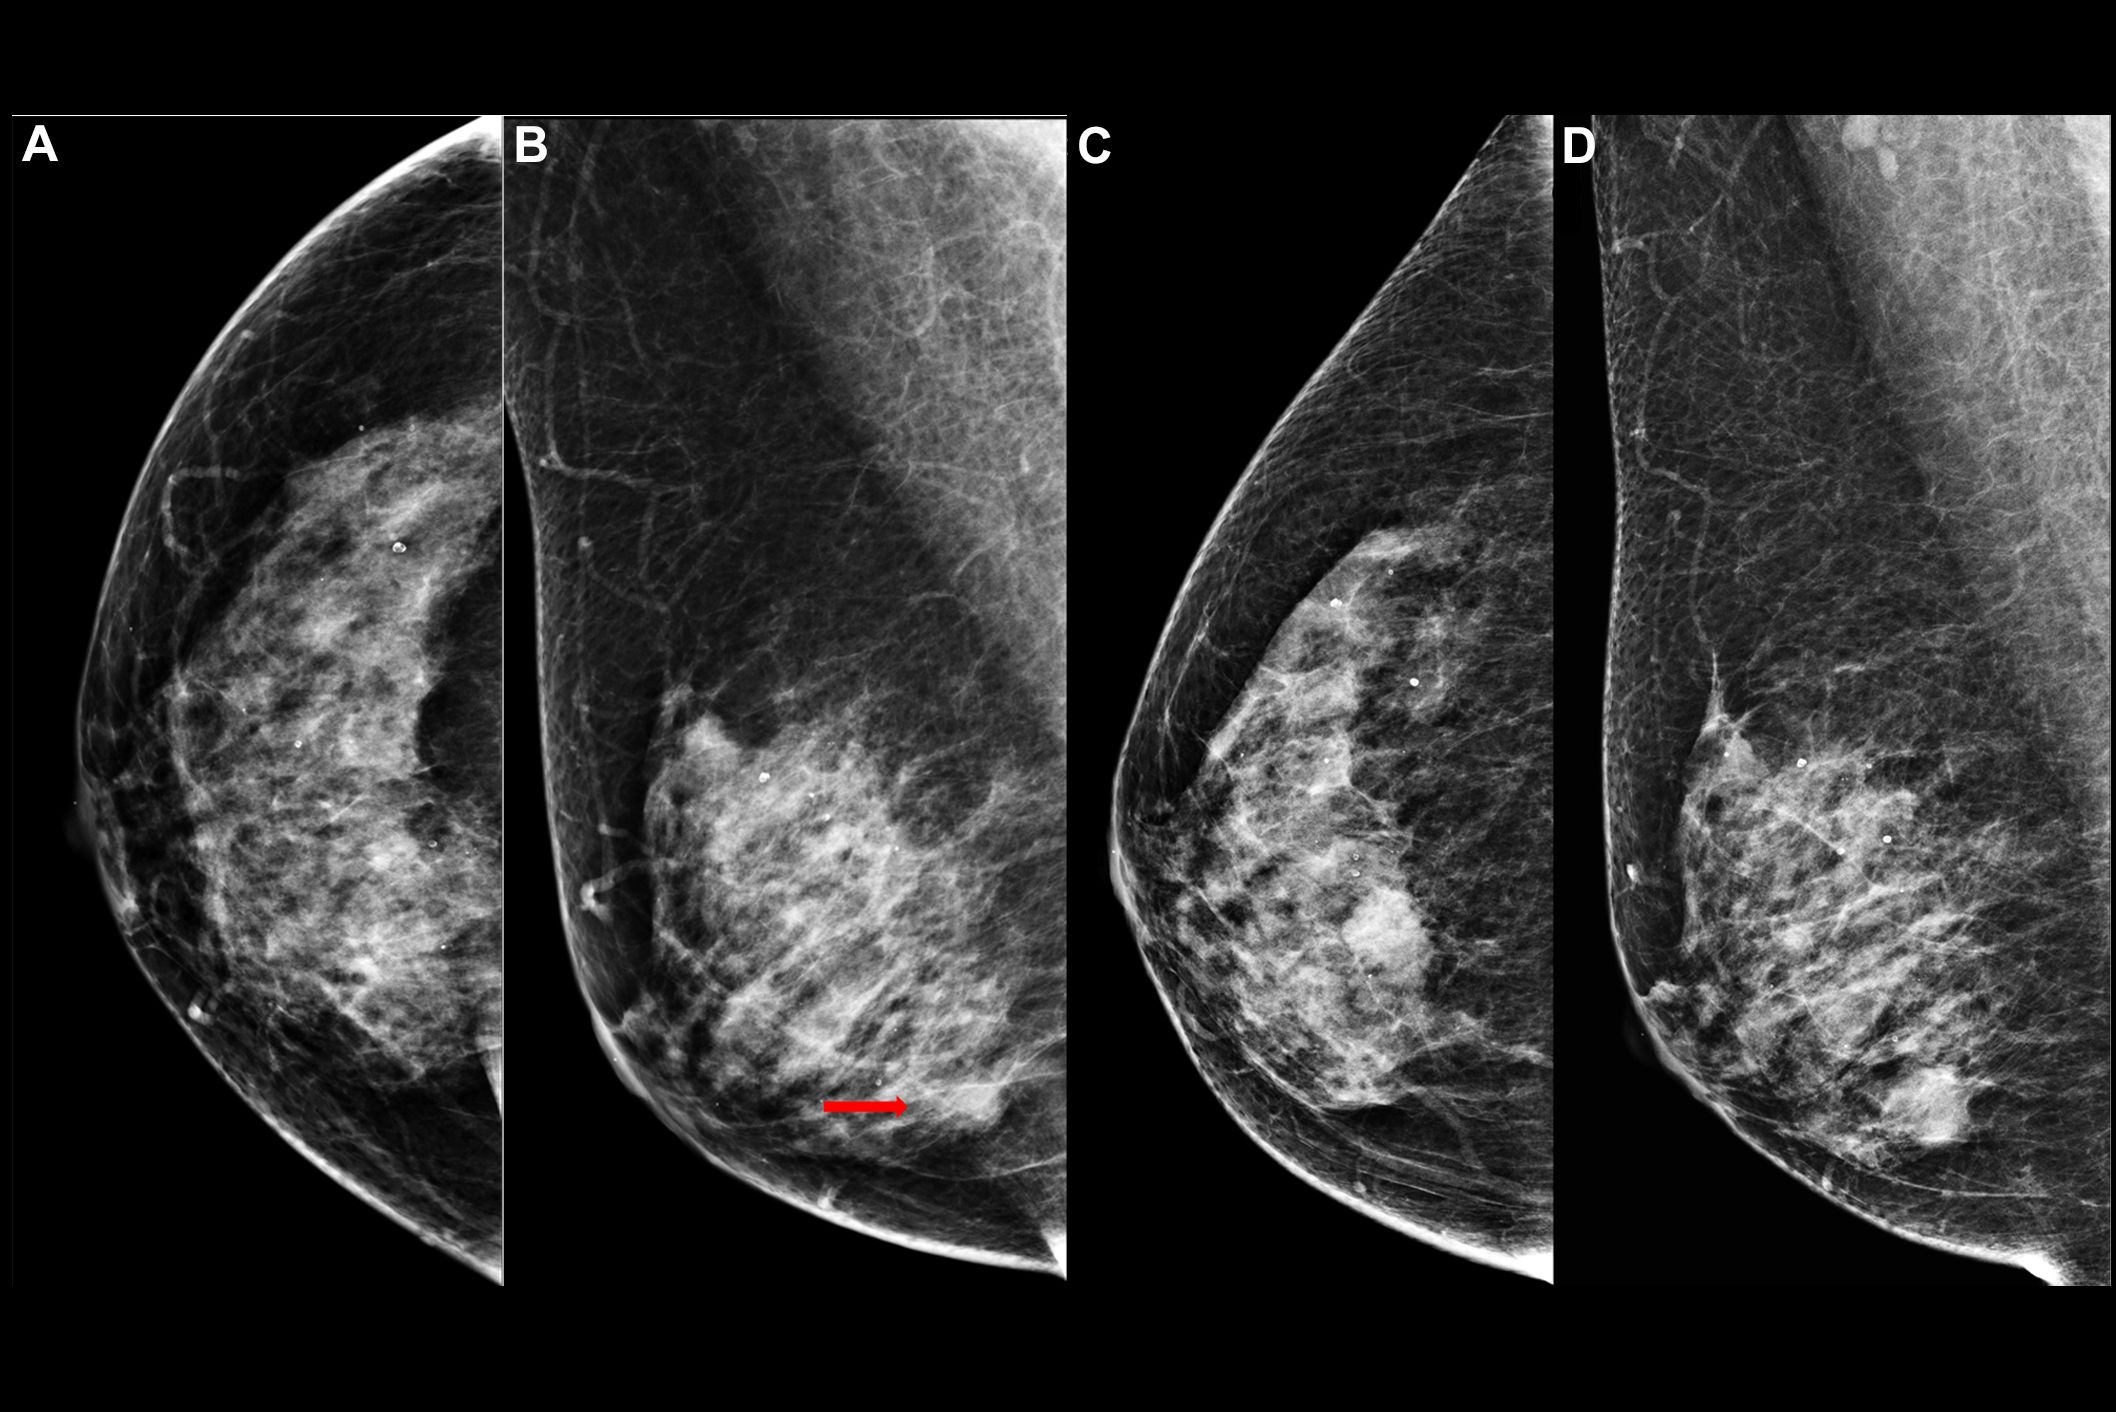

While ultrasound is frequently used, its performance varies depending on operator skill and it has typically demonstrated poor repeatability. Mammography's performance suffers when imaging dense breast tissue, and MRI has shown it can both under- and overestimate residual disease (and MRI is expensive and cannot be used on patients who are allergic to contrast agents or have metal implants). However, ABVS is a new technique that covers the whole breast using an automated ultrasound system at frequencies of 5 to 15 MHz.

Peng and colleagues investigated the performance of ABVS for assessing residual breast tumor size after neoadjuvant therapy, comparing it to hand-held ultrasonography, mammography, and MRI.